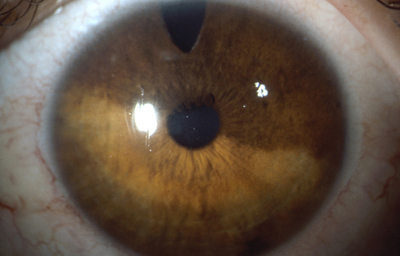

En los humanos y en la mayoría de los mamíferos y pájaros, el Iris es una estructura anular en el ojo, responsable de controlar el diámetro y tamaño de la Pupila y controlar así la cantidad de luz que penetra al Ojo. En términos de la Optica, el Iris es el diafragma y la pupila su apertura. El color del ojo se define según el color del Iris.

Separa la cámara Anterior de la cámara Posterior en el Ojo, y esta situado por delante del Cristalino; se compone de 3 capas: la hoja Anterior del Iris (membrana pupilar) cuya atrofia parcial genera las criptas de Fuch´s, el Estroma, capa fibrovascular y pigmentada, no tiene epitelio y su origen es mesodérmico; la Posterior debajo del estroma, es una capa de células epiteliales pigmentadas con un grosor de 2 células, conocida como el Epitelio pigmentario del Iris cuyo origen viene del neuroectodermo.

1- La Zona Pupilar es la región mas interna que conforma el borde de la pupila ;(desde el borde periférico del collarete)

2- La Zona Ciliar es el resto del iris y se extiende hasta su origen en el cuerpo ciliar

El Collarete que separa la zona pupilar de la ciliar y es la porción mas gruesa del iris, es un vestigio de la cubierta de la pupila embrionaria. La Raiz de iris es la porción mas periférica y la mas delgada, esta unida a la esclera y a la porción anterior del Cuerpo Ciliar. El Iris y el Cuerpo Ciliar componen la Úvea Anterior.

En la cara Anterior esta el pigmento que le da el color al Iris y dependiendo del grado de reabsorción u atrofia de esa capa anterior se pueden observar:

Las Criptas de Fuchs: que son pequeñas aberturas alrededor del collarete, producto de la atrofia o reabsorción de la hoja anterior del iris, que le permiten al estroma y a los tejidos mas profundos estar en contacto con el humor acuoso.

Cuando el Iris no tiene criptas, se considera que la reabsorción u atrofia de la hoja anterior (memb. pupilar) se detuvo en el circulo menor.